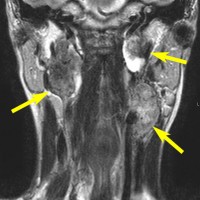

左は1991年,右は2006年のMRI画像です。15年間で腫瘍のサイズは変わっていません。

1991年に50代の女性にみつかったものでした。黄色に示したルートで摘出できないわけではありませんが,右後頭部が腫れてきたという訴えとホルネル症候,軟口蓋麻痺しかなかったので,何も治療しないでほっておきました。2016年まで25年間観察し続けました。症状の悪化は全くなく元気に暮らしておられます。グロームス腫瘍はある一定の年齢になると増大しないという性質を持っている良性腫瘍です。これを大々的な頭蓋底外科手術で摘出するするという愚を犯してはなりません。

遺伝歴があり30代くらいです。黄色の矢印で示す右側はglomus vagale,左側は上がglomus jugulare、左下がglomus caroticumです。教科書に載せたいくらい典型的な部位に発生しています。無症状ですからもちろん治療はしません。6年くらい経過観察していますがほとんど増大もしません。